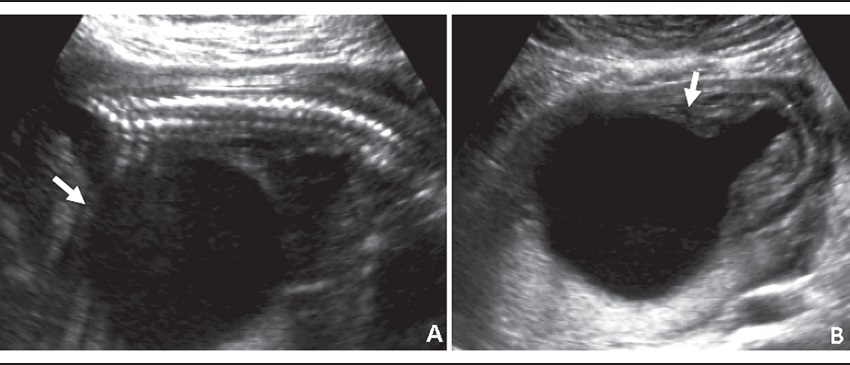

V. G. was a 21-year-old pregnant woman for the first time referred for the high-risk prenatal care due to an alteration in obstetrical ultrasound. There was an image suggestive of megabladder. The 20-week ultrasonography (USG) examination showed absence of the amniotic fluid (anhydramnios) and an enlarged bladder with narrowing of the urethra in the proximal region, suggestive of lower urinary tract obstruction (LUTO). At 21 weeks of gestation the fetal bladder was punctured for relief of obstruction, and biochemical and karyotype analysis of the material was performed. The volume of fetal urine removed was 282 ml. There were no complications during or after the procedure. The karyotype was normal (46,XY). The biochemical analysis showed the following results: potassium: 3 mEq/l (reference value: < 3 mEq/l); sodium: 109 mEq/l (reference value: < 100 mEq/l), and chlorides: 93 mEq/l (reference value: < 90 mEq/l), indicative of renal damage. Second-trimester ultrasound showed absence of amniotic fluid; increased echogenicity of the renal parenchyma, and distended bladder with "keyhole signal" (Figure 1). Fetal echocardiography was normal. The 25-week ultrasound also showed severe ascites, pericardial effusion, fetal bladder walls thickening, and the right kidney with diminished dimensions (Figure 2). The infant was born through vaginal delivery, at 27 weeks of pregnancy, weighing 1,960 grams and Apgar scores of 1 at first and fifth minutes. The infant had a significant abdominal distention and upper and lower limb deformities (Figure 3). He presented respiratory distress and evolved to death about 2 hours after birth.

LUTO comprises a heterogeneous group of pathologies associated with early-onset severe oligohydramnios. Chromosomal abnormalities associated with LUTO include Down syndrome (trisomy 21) and Edwards syndrome (trisomy 18)(1-3). Posterior urethral valve (PUV) is considered one of the most common causes of LUTO. PUV can be defined as the presence of membranes that obstruct the urethral lumen, leading to urinary retention and renal damage. It presents an incidence of 1 for every 5,000 to 8,000 live male births. The severity and degree of obstruction caused by PUV depends on the relation between the membrane and the urethra. Prenatal diagnosis of PUV is based on maternal ultrasound, with evidence, for example, of the "keyhole signal"(4). Oligohydramnios when associated with LUTO has an estimated mortality rate of 95%. This occurs due to pulmonary hypoplasia caused by the fetal compression secondary to the oligohydramnios. The mortality rate in cases of PUV is directly related to pulmonary insufficiency in 45% of the cases(1).